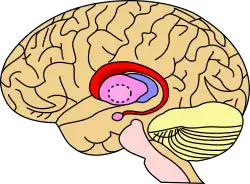

Caudate nucleus (in red) shown within the brain | |